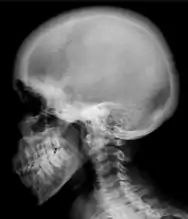

Ground glass density of the skull.[18]

Renal osteodystrophy is usually diagnosed after treatment for end-stage kidney disease begins; however the CKD-MBD starts early in the course of CKD.[1][6] In advanced stages, blood tests will indicate decreased calcium and calcitriol (vitamin D) and increased phosphate, and parathyroid hormone levels. In earlier stages, serum calcium, phosphate levels are normal at the expense of high parathyroid hormone and fibroblast growth factor-23 levels. X-rays will also show bone features of renal osteodystrophy (subperiostic bone resorption, chondrocalcinosis at the knees and pubic symphysis, osteopenia and bone fractures) but may be difficult to differentiate from other conditions. Since the diagnosis of these bone abnormalities cannot be obtained correctly by current clinical, biochemical, and imaging methods (including measurement of bone-mineral density), bone biopsy has been, and still remains, the gold standard analysis for assessing the exact type of renal osteodystrophy.[6][16]